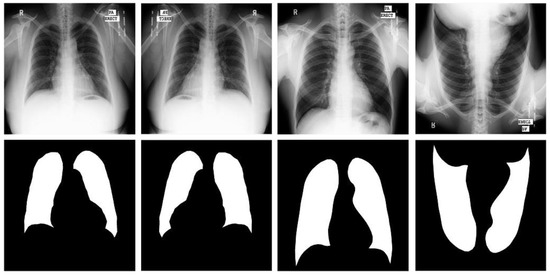

Figure 4.

Images and masks of the MC dataset.